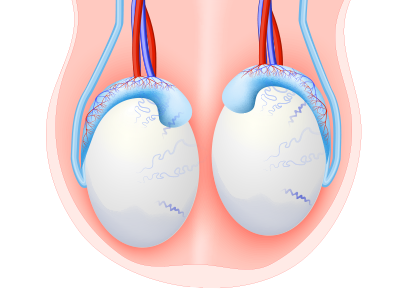

고환은 정자와 테스토스테론을 생성하는 중요 기관입니다. 고환/부고환염, 고환염전, 정계정맥류, 음낭수종 등 고환에 발생할 수 있는 다양한 질환을 적절한 방법으로 치료해야 합니다.

고환으로 들어가는 정삭의 꼬임으로 고환으로 혈액 공급이 차단되어 고환의 통증을 유발하는 질환으로 주로 사춘기 남아에게서 많이 발생합니다.

사춘기에 고환의 성장이 진행되면서 정삭을 둘러싸고 있는 근육의 수축으로 발생할 수 있으며 극심한 고환통과 구역질, 구토가 동반될 수 있습니다.

음낭 내에 있는 정맥의 혈관이 확장되어 음낭에 울퉁불퉁한 모습으로 확장된 혈관이 관찰되는 질환입니다.

배변을 할 때 아랫배에 힘을 주게 되면 겨우 만져지는 경미한 정계정맥류가 있을 수 있고, 심할 경우 음낭에 벌레가 기어다니는 듯한 확장된 혈관이 관찰될 수 있습니다.

고환 주위에 물이 차는 지로한으로 고환을 둘러싸고 있는 초막에 액체가 고이는 질환입니다. 액체가 점차 부풀어오르기 때문에 방치하면 커다란 종물로 만져질 수 있습니다.

소아의 경우 고환을 둘러싸고 있는 초막이 복강과 연결되어 있어서 복강 내 복수가 음낭내로 내려와 발생할 수 있으며, 성인의 경우 초막 내에 정상적으로 존재하는 고환수에 대한 분비과 흡수 사이의 불균형에 의해 발생합니다.